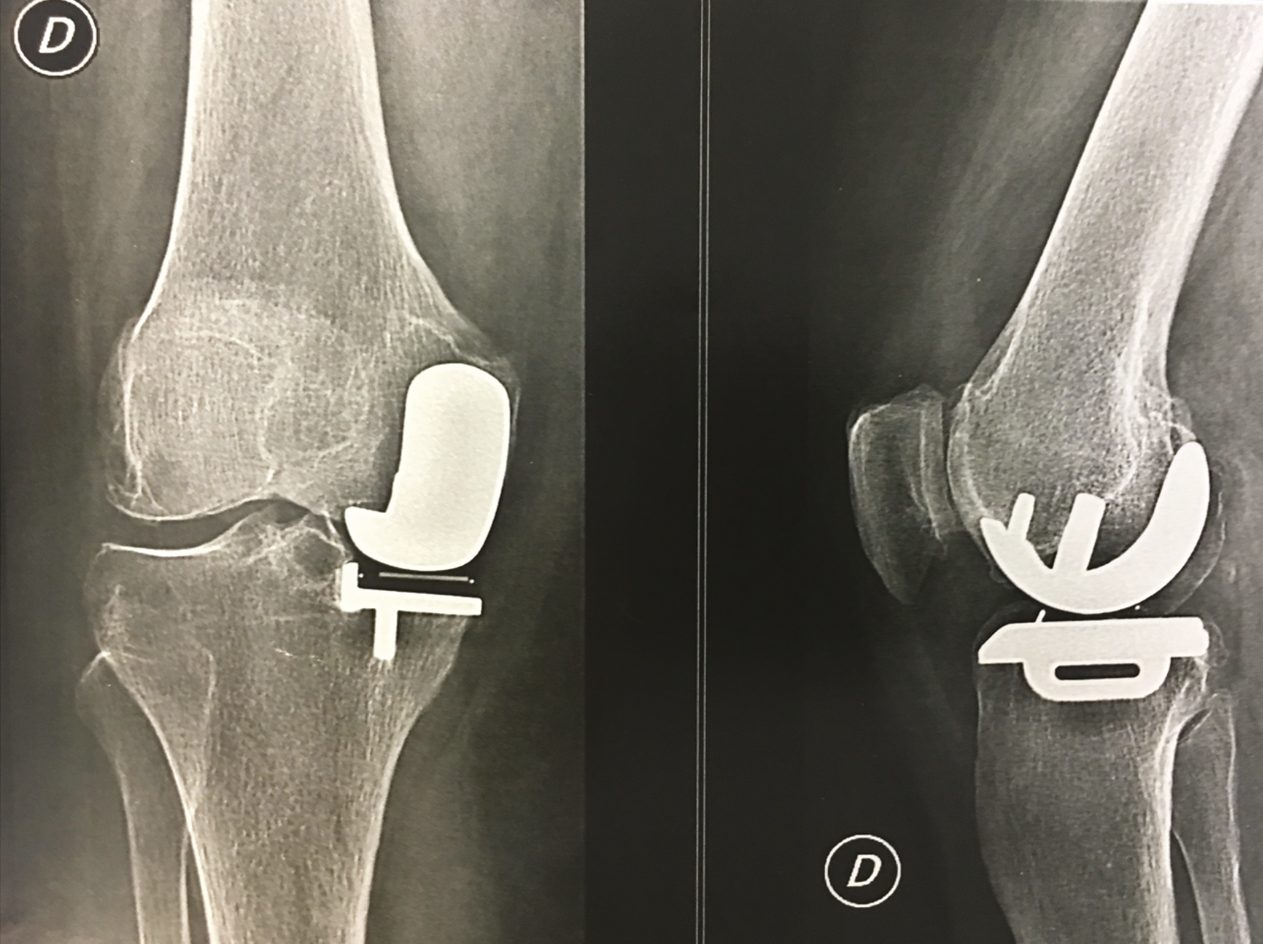

At 15 years, the clinical results for the Oxford 3 were excellent, [58] H. Pandit, T. Hamilton, C. Jenkins, S. Mellon, C. Dodd, D. Murray “The Clinical Outcome of Minimally Invasive Phase 3 Oxford Unicompartmental Knee Arthroplasty: A 15-Year Follow-up of 1000 UKAs,” The Bone & Joint Journal. 2015; 97B: 1493–1500 confirming the findings of Price & Svard [59] A. Price, U. Svard. A second decade lifetable survival analysis of the Oxford uni-compartmental knee arthroplasty. Clin Orthop Relat Res. 2011; 469:174–179. and Liddle [60] A. Liddle, A. Judge, H. Pandit, D. Murray. Determinants of revision and functional outcome following unicompartmental knee replacement. Osteoarthritis Cartilage. 2014 ; 22 :1241–1250. who had recorded 92% implant survival at 20 years for the Phase 1 and 2 Oxford models (Figs. 17 & 18).